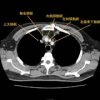

Redo AVR and Ascending Aortic Replacement With LVOT Enlargement Due to Endocarditis 2025/7/9 胸部外科 韓国ドラマを無料で見る方法 見逃したドラマ・映画・アニメを無料で見る方法 Redo AVR and Ascending Aortic Replacement With LVOT Enlargement Due to Endocarditis Learn more on CTSNet: …